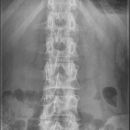

Lendenwirbelsäule a.- p.

Indikation

Fraktur und degenerative Veränderungen, Skoliose

Lagerung

Rückenlage, Arme auf Brust oder seitlich am Körper

Beine angewinkelt

Zentralstrahl

ZS senkrecht auf Objekt- und Detektormitte

Quer: 1-2 QF über oberen Beckenkamm

Bemerkung

möglichst bei Atemanhalten

auch im Stehen möglich (orthopädisch)

Gegenkontrolle: unteres Licht 2 QF über Symphysenrand

Qualitätskriterien

Scharfe und orthograde Abbildung aller Lendenwirbel mit ihren Querfortsätzen, der Kreuzdarmbeingelenke und des thorakolumbalen Überganges. Die Dornfortsätze sind mittelständig. Zwischenwirbelraum frei projiziert.